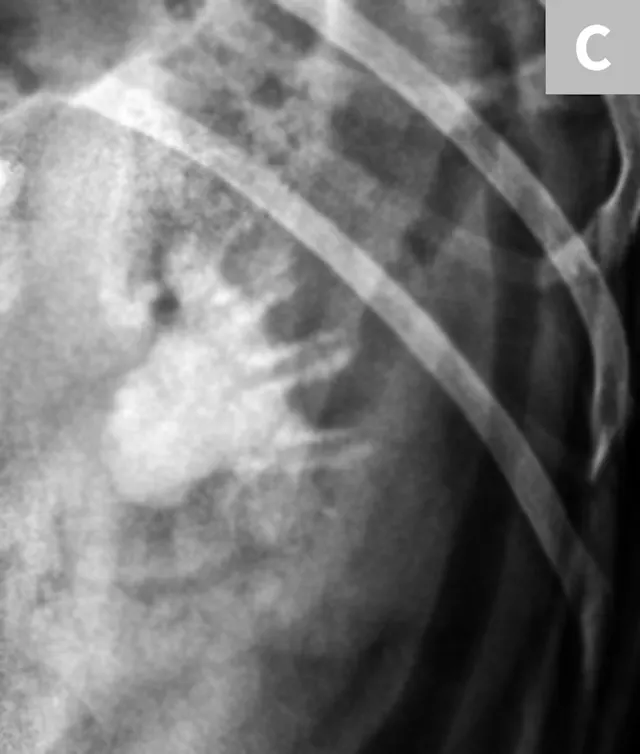

A separate center of ossification associated with the os penis may mimic a urethral calculus (Figure 11 A and B). A separate center of ossification can be seen at either end of the os penis and will be in line with the os penis. A calculus within the penile urethra would be seen ventral to the os penis in the location of the urethra. Contrast urethrography can be a helpful way to differentiate between a separate center of ossification and urethral calculus (Figure 11C).

FIGURE 11A

Lateral radiograph of a male dog collimated to include the urinary bladder and os penis. Note the well-defined mineral opacity just proximal to and at the same level as the base of the os penis—a separate center of ossification (arrow). Also note the two soft tissue opaque nodules summating with the prepuce, presumed to be small nipples (arrowheads).